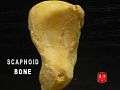

Scaphoid bone

Scaphoid bone of the left hand. Close up. Animation. Scaphoid bone.